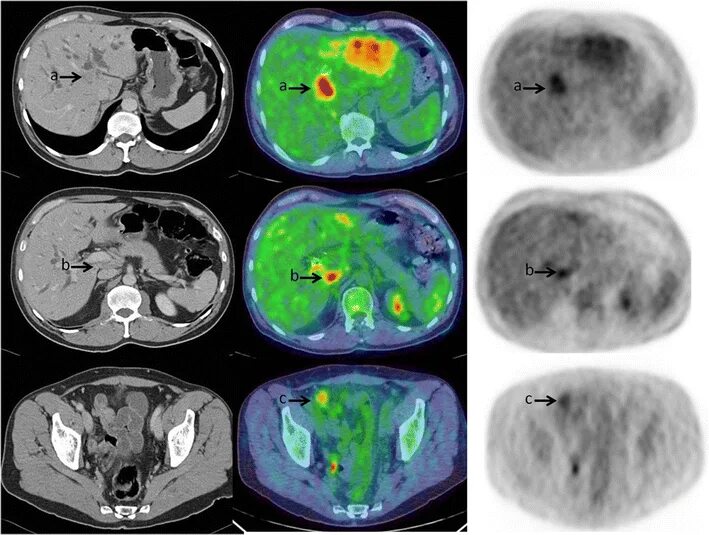

Плохо после контраста кт